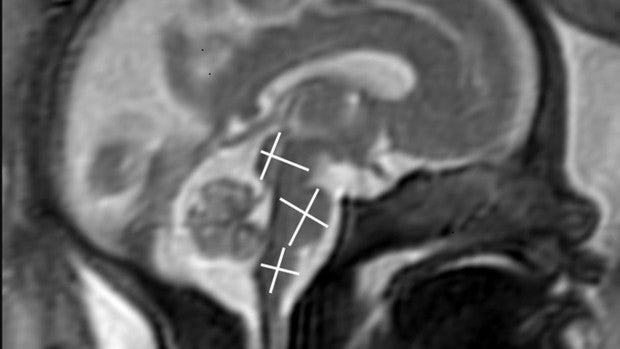

La infección grave leve a moderada por Covid-19, no tiene ningún efecto en el cerebro del feto en desarrollo, según un estudio presentado hoy en la reunión anual de la Sociedad Radiológica de América del Norte. Dos años después del inicio de la pandemia existe la certeza de que las mujeres embarazadas son más vulnerables al virus SARS-CoV-2. Sin embargo, todavía se sabe poco sobre las posibles consecuencias que puede sufrir el feto si la madre se infecta durante el embarazo. «A las mujeres infectadas con SARS-CoV-2 durante el embarazo les suele preocupar que el virus pueda afectar al desarrollo del feto, como ocurre en el caso de otras infecciones víricas», apunta la autora principal del estudio, Sophia Stöcklein, del Departamento de Radiología en la Universidad Ludwig Maximilian de Munich. «Hasta ahora, aunque existen algunos informes de transmisión vertical al feto, el riesgo y el impacto exactos, siguen sin estar claros. El objetivo de nuestro estudio fue estudiar sobre el efecto de la infección materna de la enfermedad en el desarrollo del cerebro fetal». Stöcklein y sus colegas utilizaron la resonancia magnética fetal para estudiar a 33 embarazadas con infección por Covid-19 durante el embarazo. Las pacientes tenían aproximadamente 28 semanas de embarazo, de promedio, y los síntomas aparecían alrededor de las 18 semanas de embarazo. Los síntomas maternos más comunes fueron pérdida o disminución del sentido del olfato y del gusto, tos seca, fiebre y dificultad para respirar. «A través de este análisis se descubrió que el desarrollo del cerebro era el estándar para la edad de todos los fetos. No hubo síntomas indicativos de infección del cerebro». «Este hecho debería ayudar a tranquilizar a los padres afectados», añade Stöcklein. La parte negativa del estudio es que sólo se incluyeron en el estudio a mujeres con síntomas leves a moderados y sin hospitalización. «A través de este análisis se descubrió que el desarrollo del cerebro era el estándar para la edad de todos los fetos. No hubo síntomas indicativos de infección del cerebro» Dado que no se ha determinado de manera concluyente el no impacto de una infección grave en el desarrollo del cerebro del feto, la protección activa contra la infección por SARS-CoV-2 durante el embarazo sigue siendo importante» añadió. Se recomienda como forma de protección, la vacunación para todas las personas mayores de 12 años, incluidas las mujeres que están embarazadas o que piensan quedarse embarazadas» «Hasta ahora, la vacunación es la protección más efectiva contra Covid-19», finaliza Stöcklein. «Cualquier efecto secundario es manejable, incluso en este estado. Por lo tanto, a pesar de los alentadores resultados de nuestro estudio, las embarazadas deben vacunarse, sin duda» . Con el fin de que el estudio sea más completo, los investigadores seguirán a las durante los próximos cinco años, se incluirá una evaluación neonatal detallada, además de la valoración de su desarrollo neurológico.Fuente Salud https://ift.tt/317QxAt